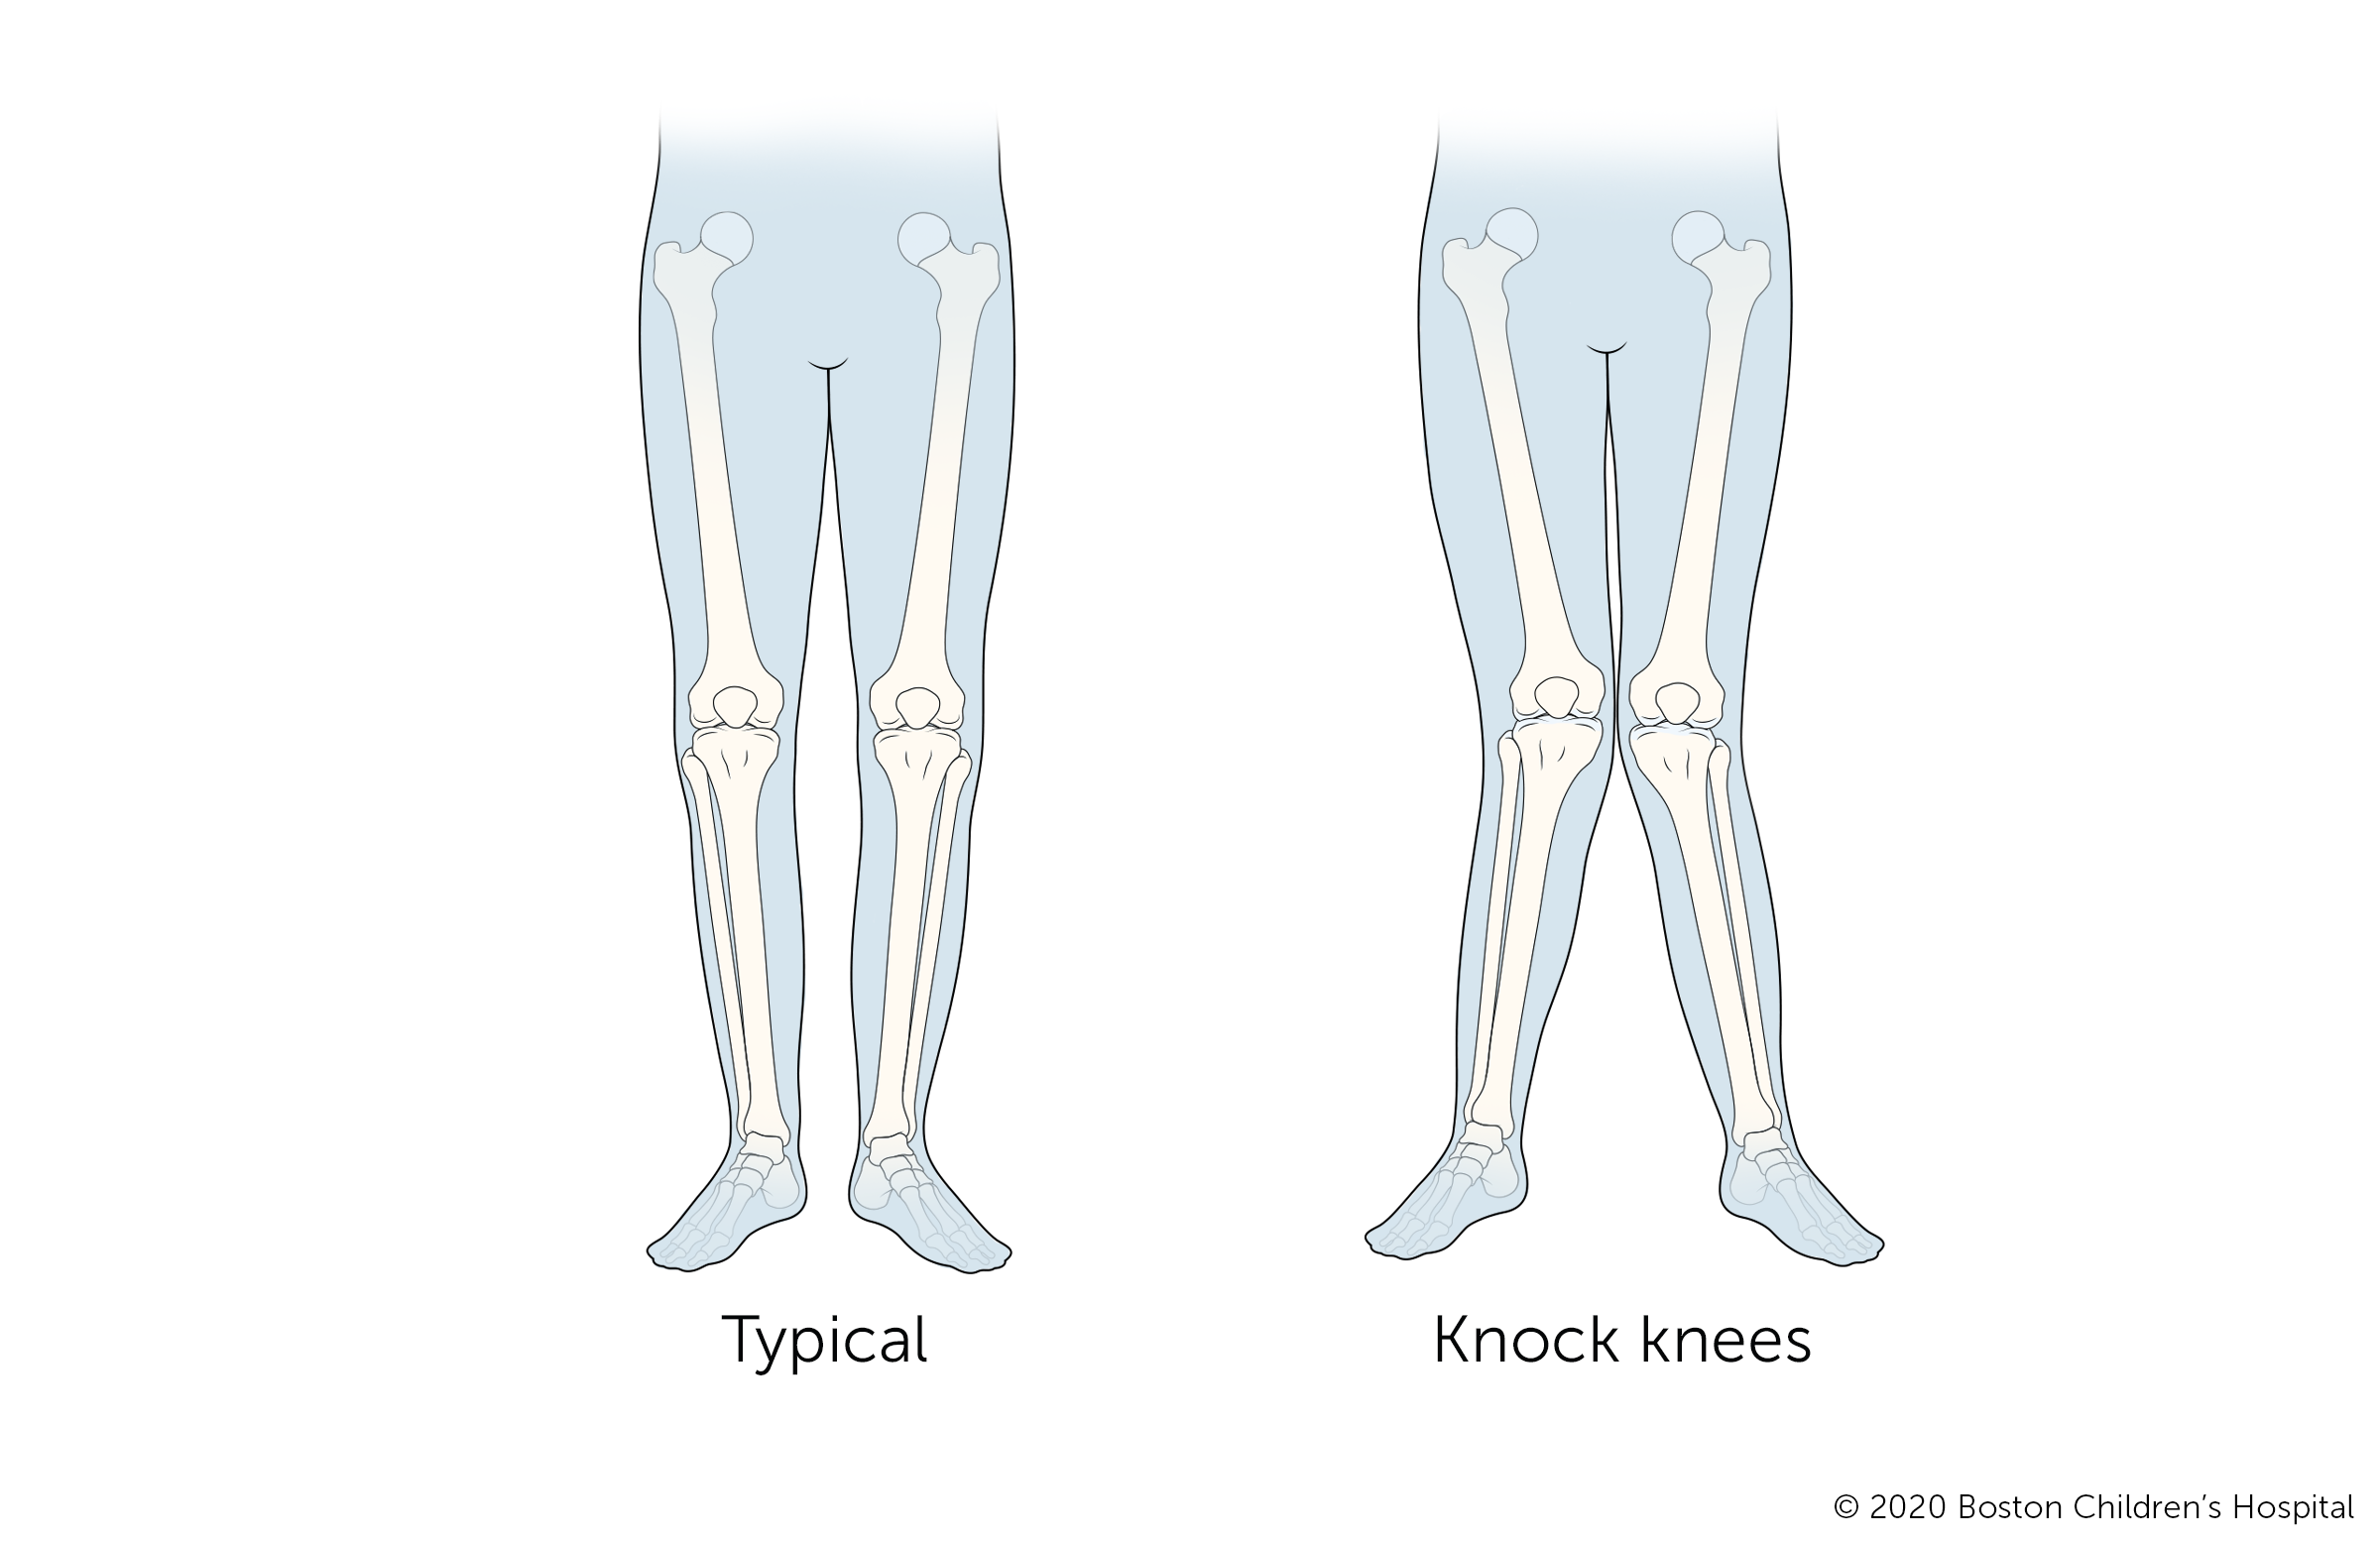

Knock knees (genu valgum) is a condition in which the knees tilt inward while the ankles remain spaced apart. The condition is slightly more common in girls, though boys can develop it too.

The symptoms of knock knees are visible when a child stands with their legs straight and toes pointed forward. Symptoms include:

- Symmetric inward angulation of the knees

- Ankles remain apart while the knees are touching